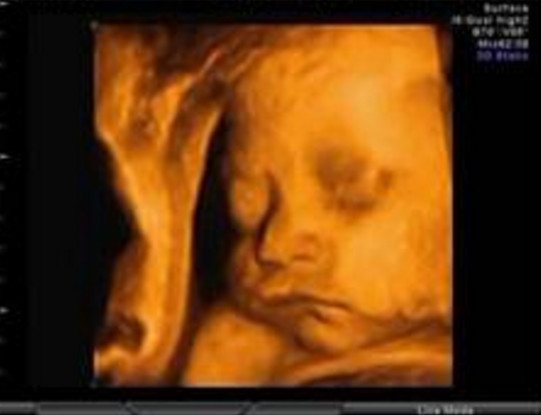

27岁的曹女士,已经怀孕六个月了。三天前,“孕味十足”的她,在丈夫的陪同下来到医院,准备进行提前预约好的四维彩超检查。但是万万没想到,检查结果让她的心情一下跌入低谷!通过影像显示,胎儿嘴唇中间竟然有一指宽的裂痕。经过医生再次仔细确认,腹中的胎儿确实患有唇腭裂,也就是“兔唇儿”。